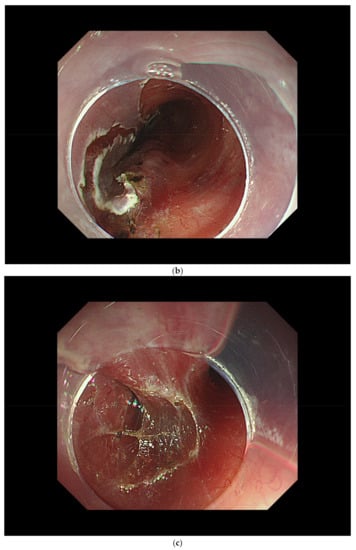

3.2. Diagnosis of Cancer Invasion Depth by White-Light Endoscopy and Magnifying Endoscopy

4.3. ER Procedure